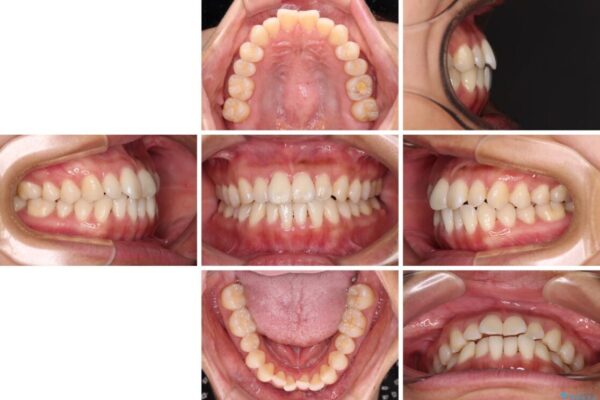

治療途中

• 【モニター】前歯のデコボコをインビザラインで改善 治療途中画像

治療後

• 【モニター】前歯のデコボコをインビザラインで改善 治療後画像